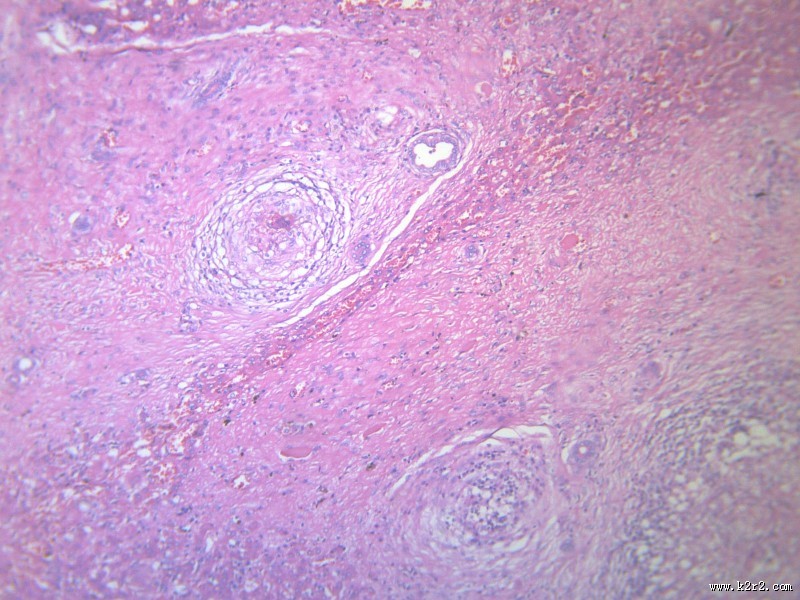

虫卵肉芽肿 - 第9张